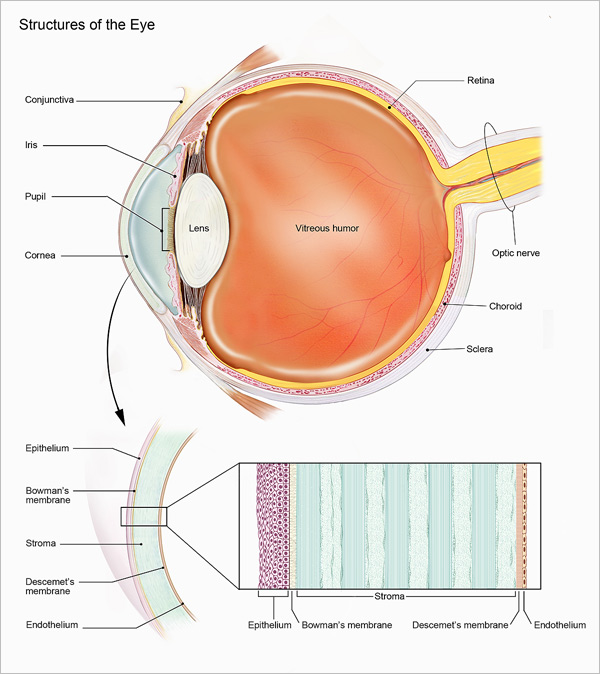

Biology-How our eyes work – Howthingswork.org

1 Anatomy of the Vitreous, Retina, and Choroid | Ento Key

Lab 35: Eye Structure Flashcards | Quizlet